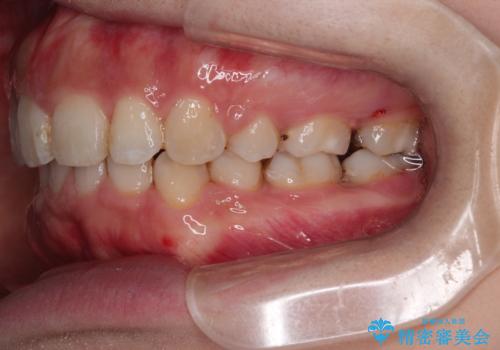

がたがたと出っ歯を直したい ワイヤーによる抜歯矯正

- ガタガタと出っ歯を主訴に来院されました。

上下左右の歯を1本ずつ、合計4本抜歯してワイヤーにて矯正治療をすることとなりました。

通常より治療期間を要しましたが、健康な歯を残すことができました。